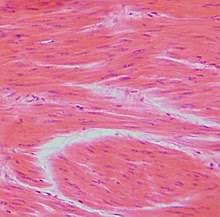

Vědci z University of British Columbia použili umělé bílkoviny na vytvoření biomateriálu, který svými vlastnostmi připomíná svalovou hmotu.

Vytvořený protein má molekulární strukturou podobnou titinu, který svalům zajišťuje jejich elastititu.

Umělá verze je však stonásobně menší než titin.

Podařilo se tak napodobit jednu ze specifických vlastností svalové hmoty, nikoli všechny její vlastnosti. Nově vyvinutý biomateriál může být nadále modifikován a vyvíjen, přičemmž další vývoj slibuje šanci na vytvoření látek se širokým spektrem užitečných mechanických vlastností, které dokáží napodobit různé typy svalů.

Charakteristickým znakem bílkovin podobných titinu je, že se působením napínací síly rozvinou a rozptýlí tak energii, čímž zabrání poškození tkáně.

Nově vyvinutá umělá svalová hmota je navíc biologicky snadno odbouratelná.

Umělá svalová hmota má molekulární strukturu podobnou titinu.